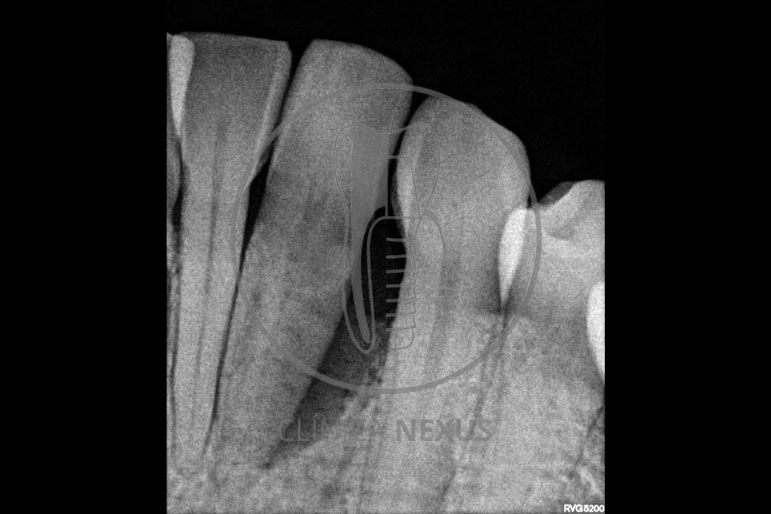

Tratamiento de defectos periodontales infraóseos en sector antero-inferior empleando gel de amelogeninas (Emdogain®) en combinación con un aloinjerto óseo (Biobank®). Paciente de 64 años, sin problemas médicos de relevancia, que presenta una periodontitis leve generalizada, pero asociada a presencia de defectos óseos verticales profundos a nivel de los espacios interdentales entre los caninos y los incisivos laterales inferiores. Tras la pertinente fase higiénica, se llevó a cabo una cirugía periodontal regenerativa, en la que, tras eliminar el cálculo subgingival (factor causal), se empleó una combinación de amelogeninas con un aloinjerto, para promover la regeneración tisular del periodonto perdido. Las imágenes clínicas y radiológicas, al año de seguimiento, reflejan un resultado terapéutico óptimo, con regeneración completa del tejido periodontal y mejora del pronóstico de los dientes involucrados.